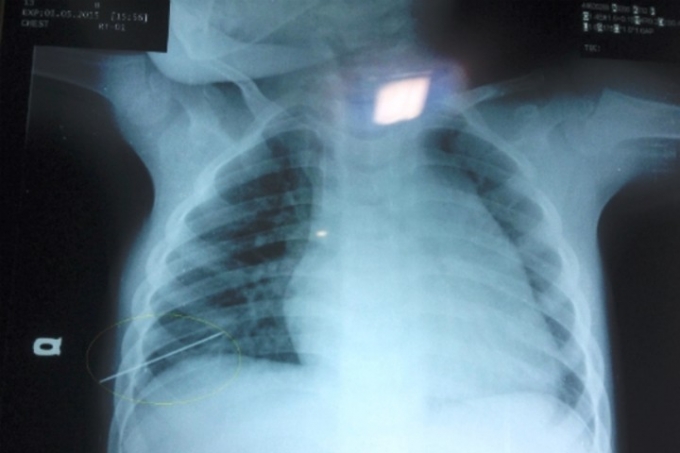

Khoảng 00h ngày 3/7/2016, sau khi bị một người lạ dùng vật nhọn đâm thủng lồng ngực bệnh nhân N.Q.V nhanh chóng được đưa tới cấp cứu tại bênh viện Chợ Rẫy. Bệnh nhân nhập viện trong tình trạng mất máu nhiều ở vết thương ngực, huyết áp 60/30; mạch 150 phút/lần.

Bệnh nhân được các bác sĩ chỉ định phẫu thuật cấp cứu và được mổ ngay tại phòng mổ của khoa Cấp cứu với sự tham gia của ekip gây mê hồi sức, bác sĩ Ngoại Lồng ngực… Ekíp phẫu thuật đã tiến hành khâu vết thương tâm thất trái, khâu thùy lưỡi phổi phải và truyền 7 đơn vị máu.

Đến 2h ngày 3/7/ 2016, ca mổ hoàn thành, cứu bệnh nhân vượt qua được ranh giới mong manh giữa sự sống và cái chết.

Sau ca phẫu thuật bệnh nhân đã tạm qua cơn nguy hiểm, sức khỏe dần ổn định. Hiện tại, bệnh nhân vẫn đang được sử dụng thuốc vận mạch, được thở máy và có thể tiếp xúc.